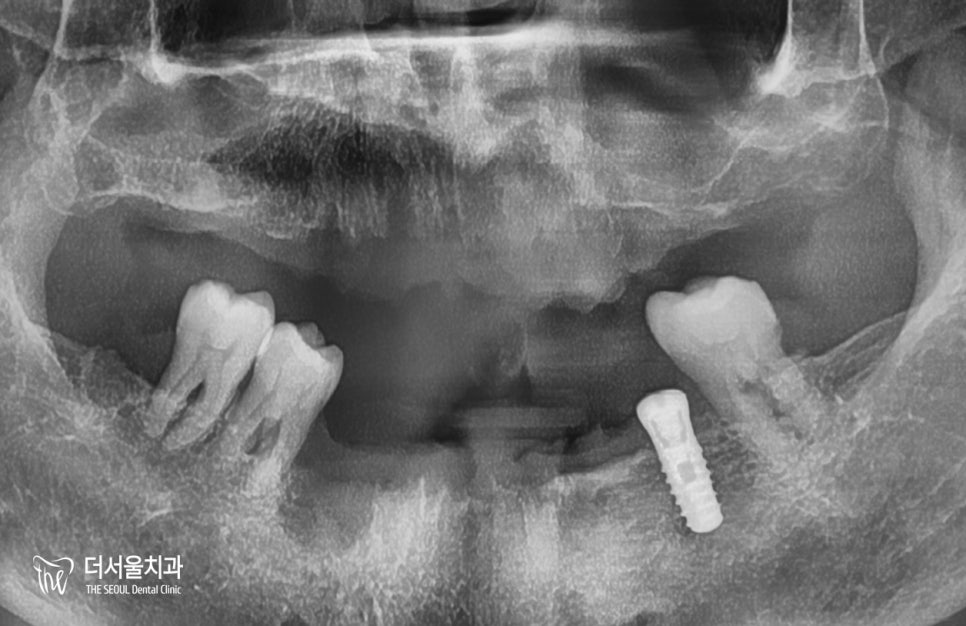

엑스레이 그리고 CT를 통해

한번 더 꼼꼼히 확인을 해서

잘 들어갔는지 봅니다.

계획했던 대로 잘 들어갔네요. ^^

그리고 한달 뒤,

아래 부분도 마찬가지로

임플란트 수술이 이뤄졌습니다.

식립하고 엑스레이와 CT를 찍어봤는데,

좋은 결과가 나왔네요. ^^